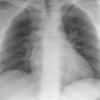

Normal PA Female

Date: 12/06/2014

Views: 6218